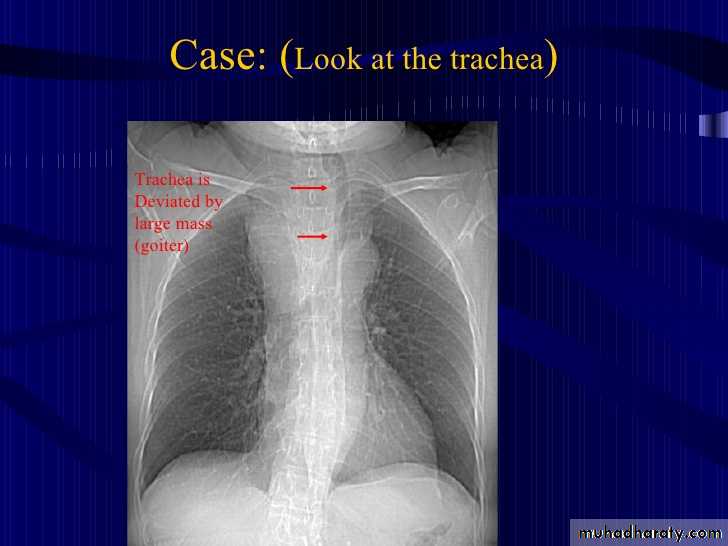

25.retrosternal Goiter

CXR , PA view shows:Widening of the superior mediastinum by soft tissue mass with deviation of the trachea to the opposite side

Retrosternal Goiter